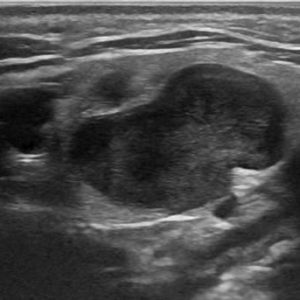

U tuyến nước bọt

Lượt xem: 170» 17-01-2021 -

U tuyến nước bọt

Lượt xem: 174» 17-01-2021 -

U tuyến nước bọt

Lượt xem: 149» 17-01-2021 -

U tuyến nước bọt

Lượt xem: 147» 17-01-2021 -

U tuyến nước bọt

Lượt xem: 146» 17-01-2021 -

U tuyến nước bọt

Lượt xem: 151» 17-01-2021 -

U tuyến nước bọt

Lượt xem: 146» 17-01-2021 -

U tuyến nước bọt

Lượt xem: 136» 17-01-2021 -

U tuyến nước bọt

Lượt xem: 132» 17-01-2021 -

U tuyến nước bọt

Lượt xem: 209» 17-01-2021 -

U tuyến nước bọt

Lượt xem: 150» 17-01-2021 -

U tuyến nước bọt

Lượt xem: 185» 17-01-2021 -

U tuyến nước bọt

Lượt xem: 151» 17-01-2021 -

U tuyến nước bọt

Lượt xem: 212» 17-01-2021 -